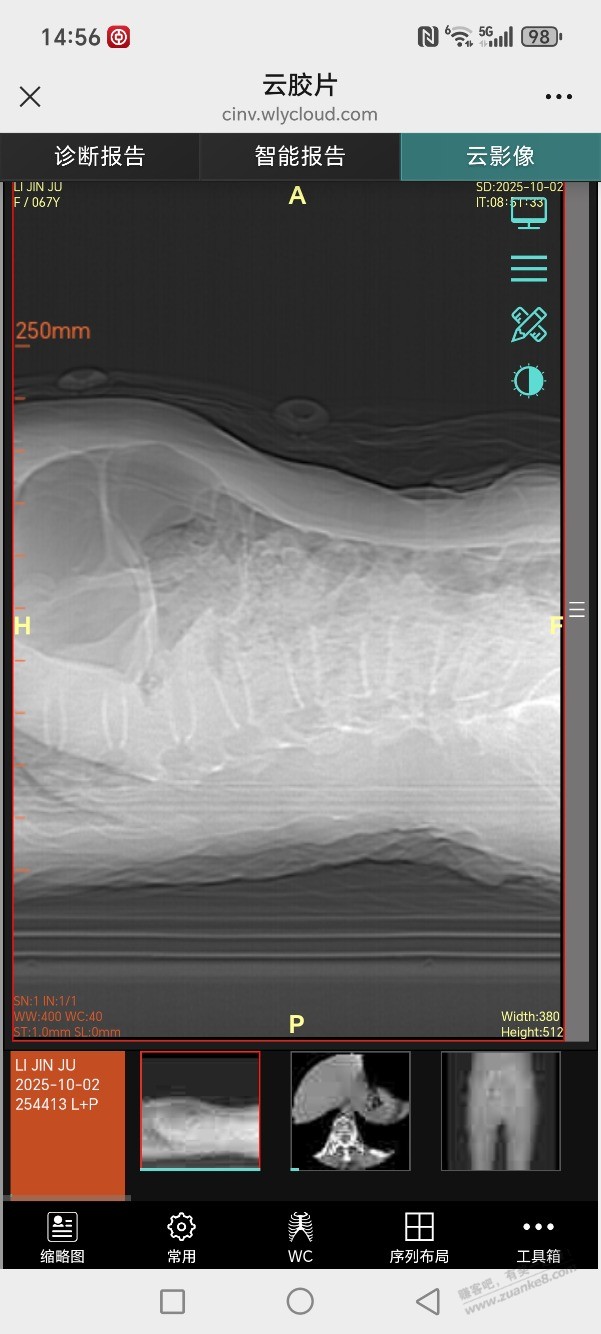

腰椎L1压缩性骨折做骨水泥手术得多少钱

镇上医生说保守治疗,市里医生让做微创骨水泥